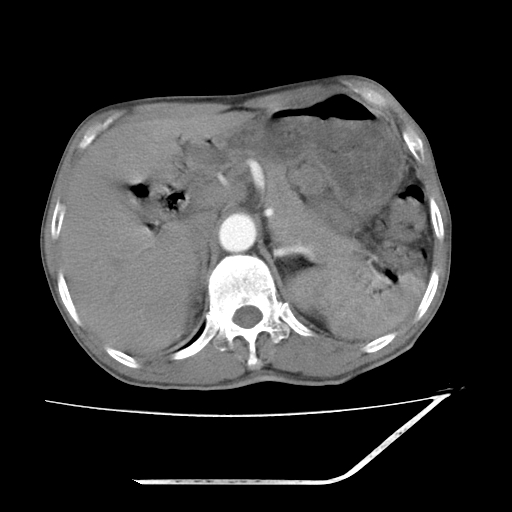

增强

考虑右肾盂癌,肾动脉受侵,右肾功能减退,右肾盂输尿管积水,管壁增厚,考虑种植转移,应该把下面扫完的

支持右侧肾盂癌伴肾静脉瘤栓形成可能性大,右肾结石.肝右叶后段低密度影,不除外转移.

右肾盂旁ca并肾静脉瘤栓形成/肾功能降低。

右肾结石。

右肾盂癌,肾动脉受侵,右肾盂输尿管积水,管壁增厚,考虑种植转移

右肾盂移行细胞癌并右输尿管中段转移.肾积水.

支持 右侧肾盂癌伴肾静脉瘤栓形成可能性大,右肾结石;肝右叶后段低密度影,不除外转移。

1.右侧肾盂癌伴肾盂积水。

2.肾脏功能减退,原因有:(1)肾动脉受侵。(2)肾静脉受侵(3)肾积水,等。本例,肾动脉显影较好,但受压明显;肾静脉无明显显示,受压或静脉癌栓,下腔静脉腔内未见明显充盈缺损。

3.右侧上段输尿管扩张,原因:(1)积水所致;(2)种植。